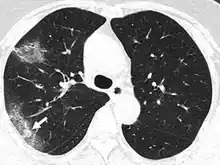

In COVID-19, the arterial and general tissue oxygen levels can drop without any initial warning. The chest x-ray may show diffuse pneumonia. Cases of silent hypoxia with COVID-19 have been reported for patients who did not experience shortness of breath or coughing until their oxygen levels had depressed to such a degree that they were at risk of acute respiratory distress (ARDS) and organ failure.[22] In a New York Times opinion piece (April 20, 2020), emergency room doctor Richard Levitan reported: "A vast majority of Covid pneumonia patients I met had remarkably low oxygen saturations at triage—seemingly incompatible with life—but they were using their cellphones as we put them on monitors."[22]